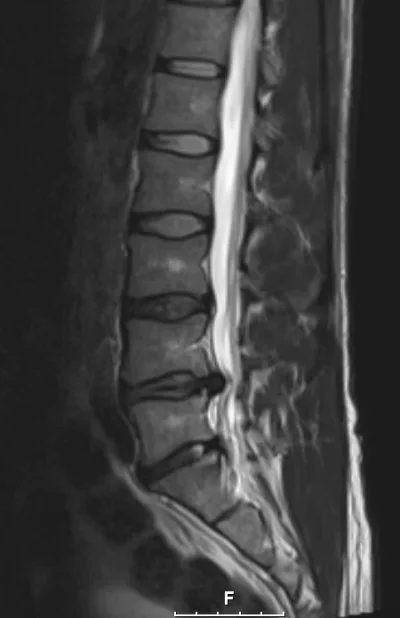

Eilisen tilanne magneetissa. Oikeasssa kankussa/lonkan seudulla ollut keväästä asti särkyä ulkokierrossa ja selällään on ollut vaikea maata. Tai oikeastaan mahdotonta niin että kankku ei olisi pienessä jännityksessä. Välillä kipu säteilee nilkkaan. Kuitenkin tuon kanssa on pystynyt elämään ja liikkumaankin kohtuullisesti.

Olen ollut sitä mieltä että kipu on lihasperäistä (tulehduksesta esim. ja liiasta autossa ja tuolilla istumisesta toimistotyöstä johtuen) ja olen sitä mieltä edelleen. Oikeastihan tuo pullistuma (joka on vasemmalla puolella) on kuvissa pahentunut, mutta vasemmalle puolelle ei kipua ole käytännössä ole ollut enää kevään jälkeen. Yksi selkä, yksi elämä. Kuvissa lokakuu 2012, maaliskuu 2013 ja joulukuu 2013.

Lekurille oli tunnin aika ja tuossa kerkesi jo oikeasti tutkia melko hyvin, lääkärillä oli aikaa kuunnella ja selittää teoriaa melko ymmärrettävästi. Tosin laskukin oli sellaiset 250€. Tuo oma pullistuma on jäätävän kokoinen kun sitä katsoo päältäpäin otetusta kuvasta. Siltikin on mielenkiintoista miten vasemmallapuolella ei ole oireita, vaikka pullistuma on siellä ja painaa selvästi hermoa. Oli myös lohdullista kuulla että jos tuo leikataan, ei kauheasti tartte ottaa stressiä siitä että pullistuma uusiutuu. Nimittäin ei ole enää sen jälkeen mitään mitä pullistua ulos. Kuvissa näkee miten ylemmässä välissä on ollut tuo annulusvaurio 9kk ajan, eikä sekään ole siitä mihinkään korjaantunut.